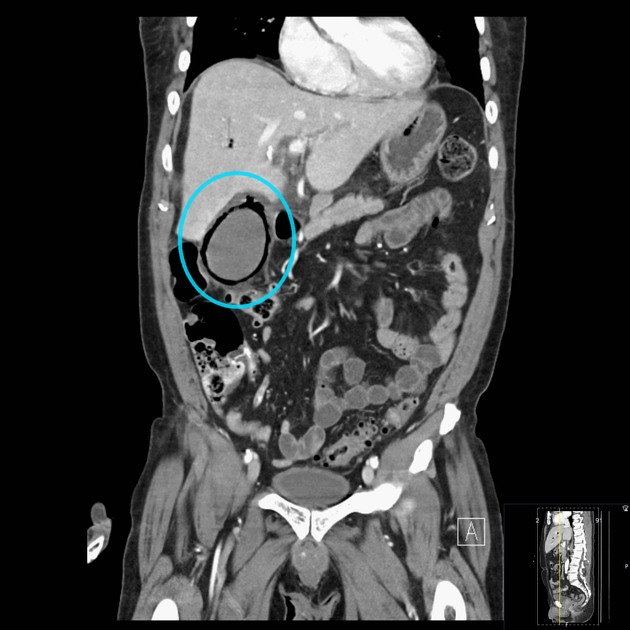

What's the Diagnosis?